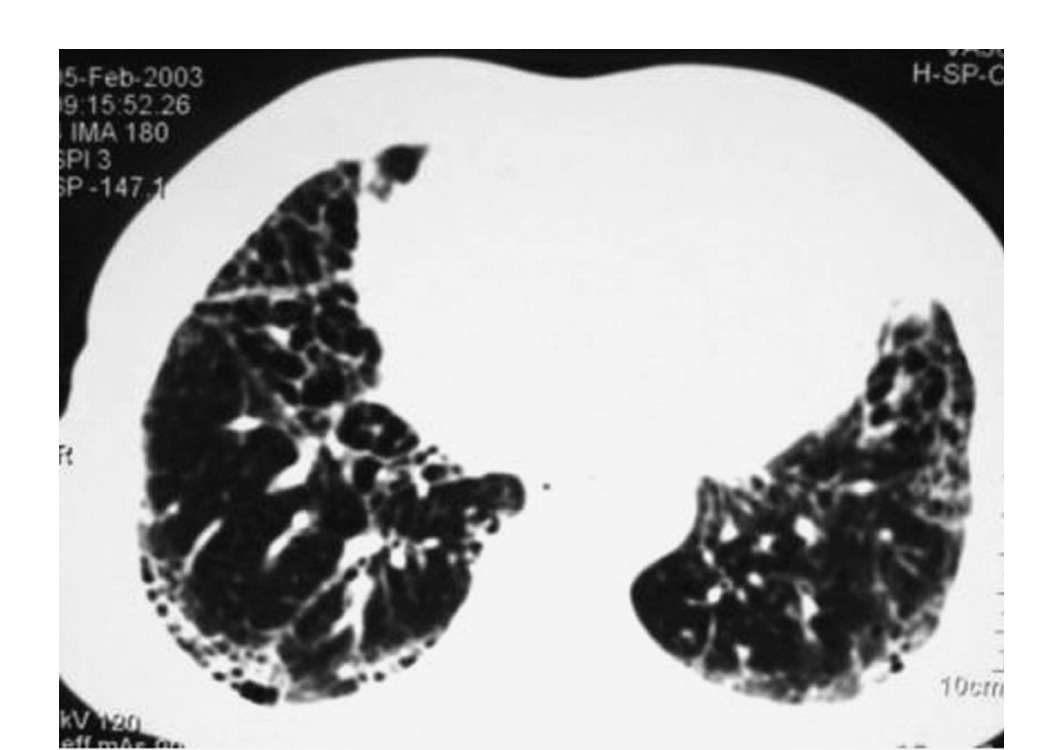

_右肺纖維化CT檢查

_特發性肺纖維化的高清CT圖像

_特發性肺間質纖維化

_特發性肺纖維化ct表現圖